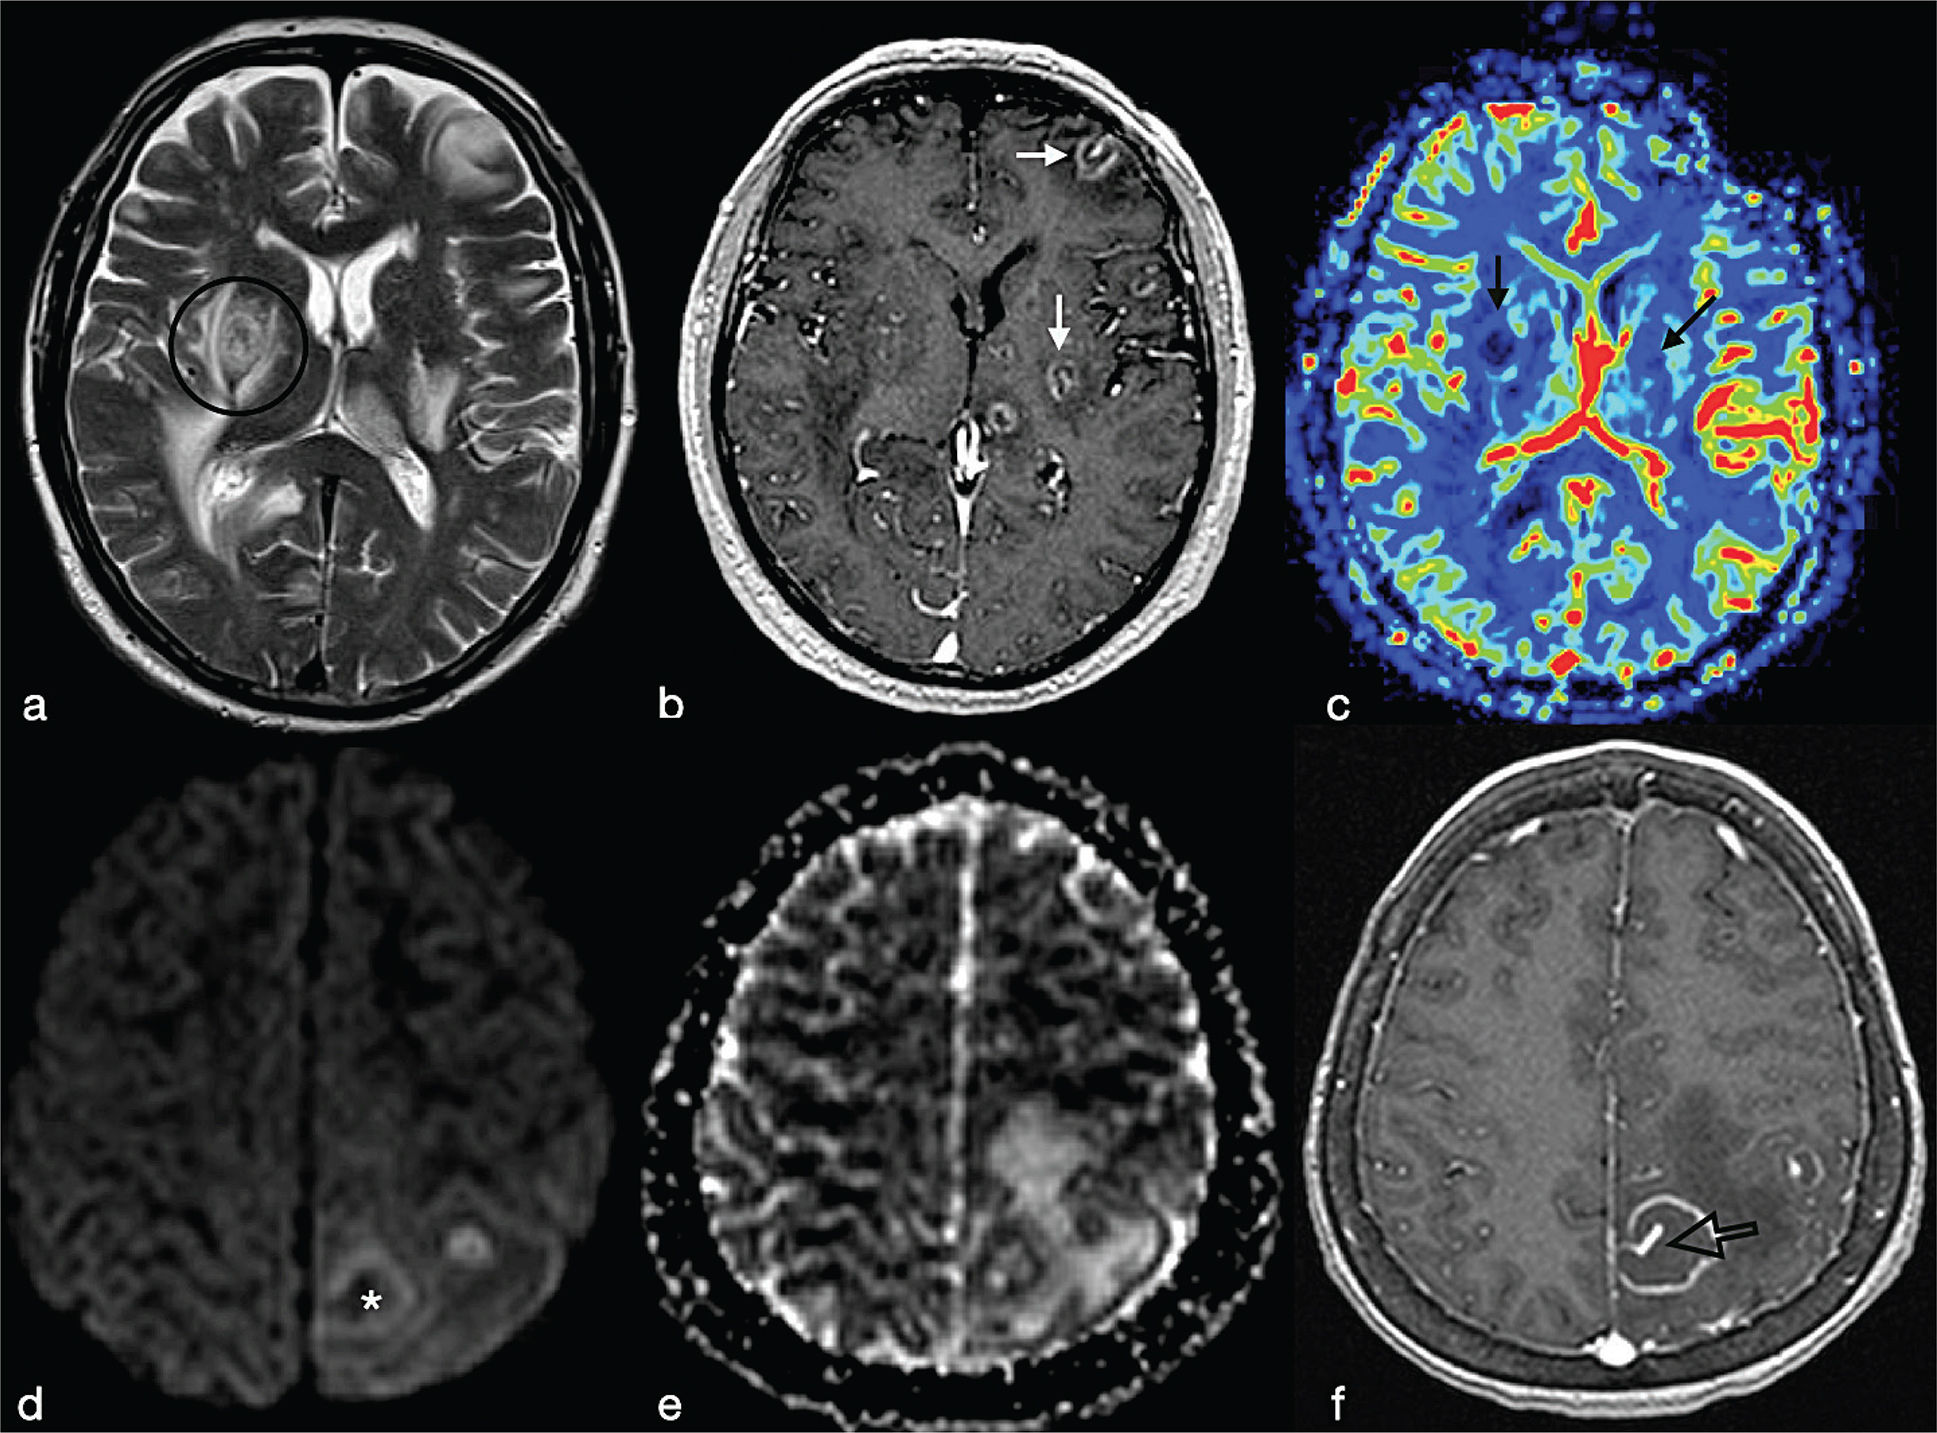

These include high-grade gliomas (WHO grade IV) and metastases. They usually exhibit a T2w hypointense, irregular or incomplete, capsular rim.8 After injection of Gd, gliomas show non-homogeneous enhancement with some nodular areas (Figure 13). Metastases, on the other hand, can exhibit an enhancement pattern similar to pyogenic abscesses. However cystic neoplasms, often have a thicker medial margin if compared with pyogenic BA (Figure 6).9 Peripheral dark signals on SWI can be also found in glioblastomas and are related to the neoplastic intralesional neoangiogenesis and haemorrhage.8 As a rule, necrotic brain tumours have high ADC values. However low ADC values have been described in hyper-cellular tumour such as metastases from lung, breast, colorectal and testicular cancer (Figure 11).5 Moreover, necrotic tumours usually show an increase of neoangiogenesis with higher values of rCBV than abscesses in the periphery of the lesion.

FIG 13. Necrotic Tumour in a 38-Year-Old Man: (a-c) a Left Temporal Lobe Cystic Mass is Shown. On T1w+Gd (c), the lesion shows irregular rim-enhancement. The central part of the lesion shows increased diffusivity (d, e) consistent with intratumoural necrotic degeneration. The rCBV map (f) showed increased perfusion within the enhancing rim of the lesion (open arrow). Final diagnosis was glioblastoma.